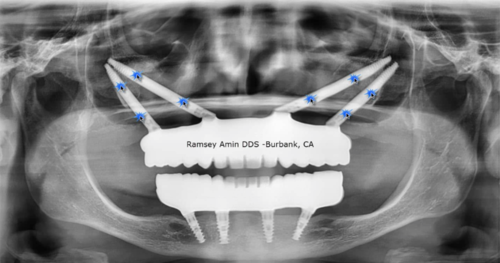

本病例最初计划进行桥体修整,并在近中种植体周围实施垂直+水平向骨增量手术。患者希望保留最后一颗天然牙,因此在等待植骨愈合期间,我将其转诊接受非手术牙周治疗,以稳定软组织。而在愈合过程中,一件令人瞩目的事情发生了:

远中种植体(LL7)开始出现自然的骨增量——此处并未进行任何植骨操作。仅仅是形成了更健康的软组织轮廓、炎症显著减轻,并为生物学自我修复创造了条件。最初,我计划拔除这颗已出现失败迹象的种植体,仅修复 LL5 和 LL6;但鉴于 LL7 周围骨量增加及组织健康状况明显改善,我们最终决定保留并修复该种植体。

我在制定治疗方案时参考了 istvanurban 关于骨再生的核心原则,但本次最大的启示却来自生物学本身。